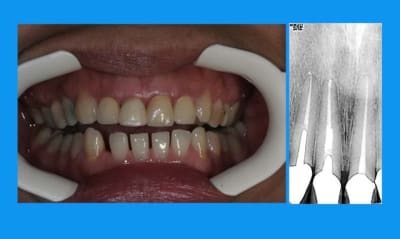

l'odf a utilisé un arc 0.014 thermique ,force constante faible

la dent provisoire a été meulée au fur et à mesure de la traction = 3mm

elle a un sourire très gingival et des prothèses déjà en place:la chir de 3 à 3 aurait été plus rapide mais peut être moins esthetique... et je n'ai pas osé....

Tu n'as donc pas nivellé la ligne des collets ?

entre temps il y a de l'odf pr réaligner les incisives du bas(diastèmes se modifient d'après la patiente), à la demande de la patiente et parceque la fracture de 11 au bout de tant d'années me questionne...

la CCM est en prov de luxe

(ça tombait bien,la teinte est moyenne,bien qu'elle passe mieux en bouche que sur la photo:le flash?)

la patiente part en vacances

je la referai en septembre

avec ou sans chir?...

il y a eu remodelage naturel(comme quoi entre la theorie et la clinique): peut on le considérer comme suffisant?